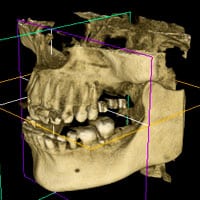

Tomografia komputerowa 3D

Technologia 3D stała się priorytetowym narzędziem diagnostycznym, umożliwiającym pełną diagnostykę rzeczywistego stanu, nie tylko zęba. Wykorzystywana jest między innymi do oceny torbieli, ułożenia zębów mądrości przed zabiegiem usuwania, wspomaga leczenie ortodontyczne w ocenie ułożenia zębów zatrzymanych, wspiera lekarza endodontę w leczeniu kanałowym trudnych przypadków.

- tomografia komputerowa szczęki i żuchwy

- tomografia komputerowa zatok

- tomografia komputerowa stawów skroniowo-żuchwowych